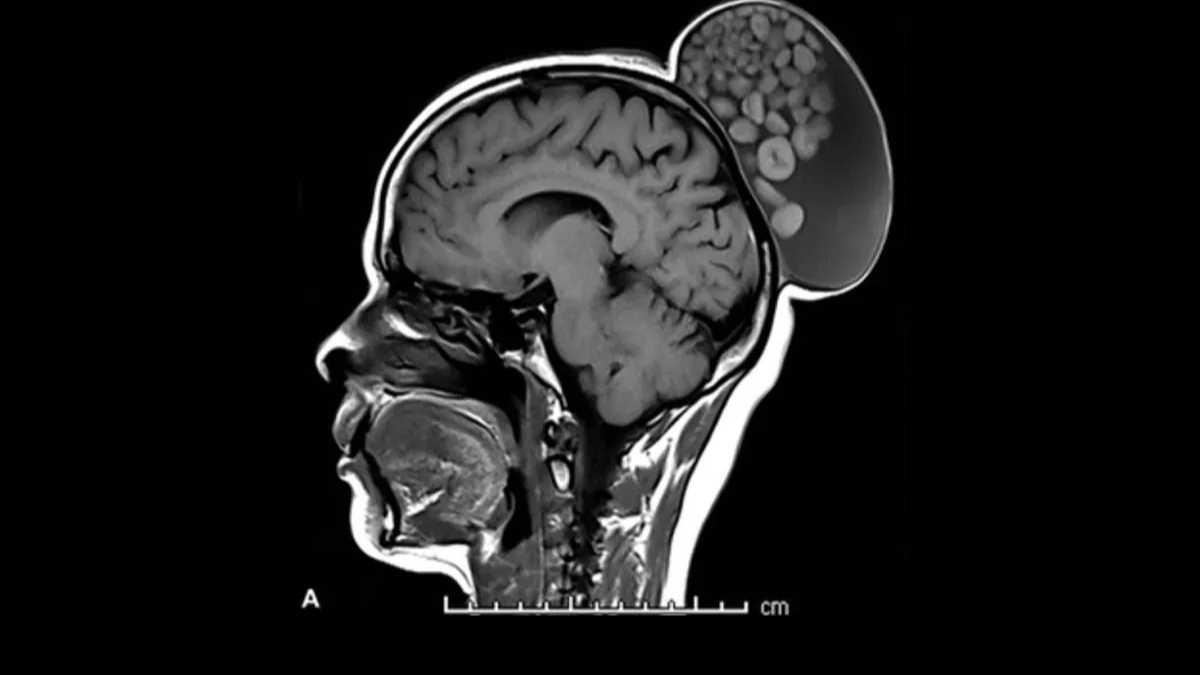

ಎಂಆರ್ಐ ಸ್ಕ್ಯಾನ್ ಮಹಿಳೆಯ ತಲೆಯ ಹಿಂಭಾಗದಲ್ಲಿ ಮಾಂಸಭರಿತ ಕೂದಲಿನ ಬನ್ನಂತೆ ಚೀಲವನ್ನು ತೋರಿಸಿತ್ತು. ಅದರ ಬೆಳವಣಿಗೆ ಹೆಚ್ಚಾಗುತ್ತಿದ್ದರಿಂದ ಆ ಬೆಳವಣಿಗೆಯ ಮಾಂಸವನ್ನು ತೆಗೆದುಹಾಕಲಾಯಿತು. ಶಸ್ತ್ರ ಚಿಕಿತ್ಸೆಯ ಬಳಿಕ ಆ ಮಾಂಸ ದ್ರವ, ಕೂದಲು ಮತ್ತು ಕೊಬ್ಬಿನ ಅಣುಗಳಿಂದ ದಪ್ಪವಾದ ಹೊರ ಮಾಂಸದಿಂದ ಕೂಡಿತ್ತು ಎಂದು ವೈದ್ಯರು ತಿಳಿಸಿದ್ದಾರೆ. ಜೊತೆಗೆ ಅದು ವಿವಿಧ ಗಾತ್ರದ ಕೆರಾಟಿನ್ ಚೆಂಡುಗಳಿಂದ ತುಂಬಿರುವುದನ್ನು ವೈದ್ಯರು ಗಮನಿಸಿದರು.